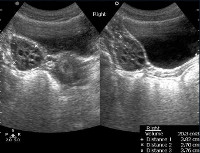

УЗИ органов малого таза девочке в детской гинекологии применяется для ранней диагностики патологических состояний репродуктивных органов в различные возрастные периоды - от раннего детства до полового созревания. УЗИ органов малого таза девочке обычно выполняется трансабдоминальным (надлобковым) доступом; реже - трансректальным или промежностным доступом. В процессе УЗИ-сканирования оценивается топографическая анатомия и размеры мочевого пузыря, шейки матки, полости матки, яичников и маточных труб. С помощью ультразвукового обследования могут быть обнаружены аномалии развития внутренних половых органов, наличие жидкости в малом тазу, кисты яичников, воспалительные изменения УЗИ органов малого таза у менструирующих девушек предпочтительно проводить на 5-10 день цикла, у девочек допубертатного возраста - в любое время.

В процессе УЗИ органов малого таза осматривается матка, яичники и мочевой пузырь. Акт осмотра содержит информацию о местонахождении и контурах матки, размерах тела и шейки матки, эхоструктуре, толщине эндометрия, состоянии матки, наличии свободной жидкости в полости таза, размерах, контурах и структуре эхо-сигналов яичников. Частью гинекологического УЗИ девочки может быть УЗИ сосудов малого таза с оценкой кровообращения.

Обычно матка находится в положении антефлексии (отклонена спереди), гиператефлексия матки считается аномалией положения, которое ухудшает течение беременности. Контуры и структура матки четкие и ровные; размеры тела и шейки матки соответствуют возрастным нормам; эхогенность мускулатуры однородна; Толщина эндометрия (М-эхо) - соответствует фазе менструального цикла. В задней части капсулы нет жидкости. Контуры здоровых яичников четкие и неровные (узелковые), из-за растущих пузырьков структура эха является однородной. Поскольку анатомо-физиологические параметры внутренних половых органов в детстве имеют свои особенности, специалист по проведению УЗИ органов малого таза должен быть хорошо знаком с возрастными нормами.